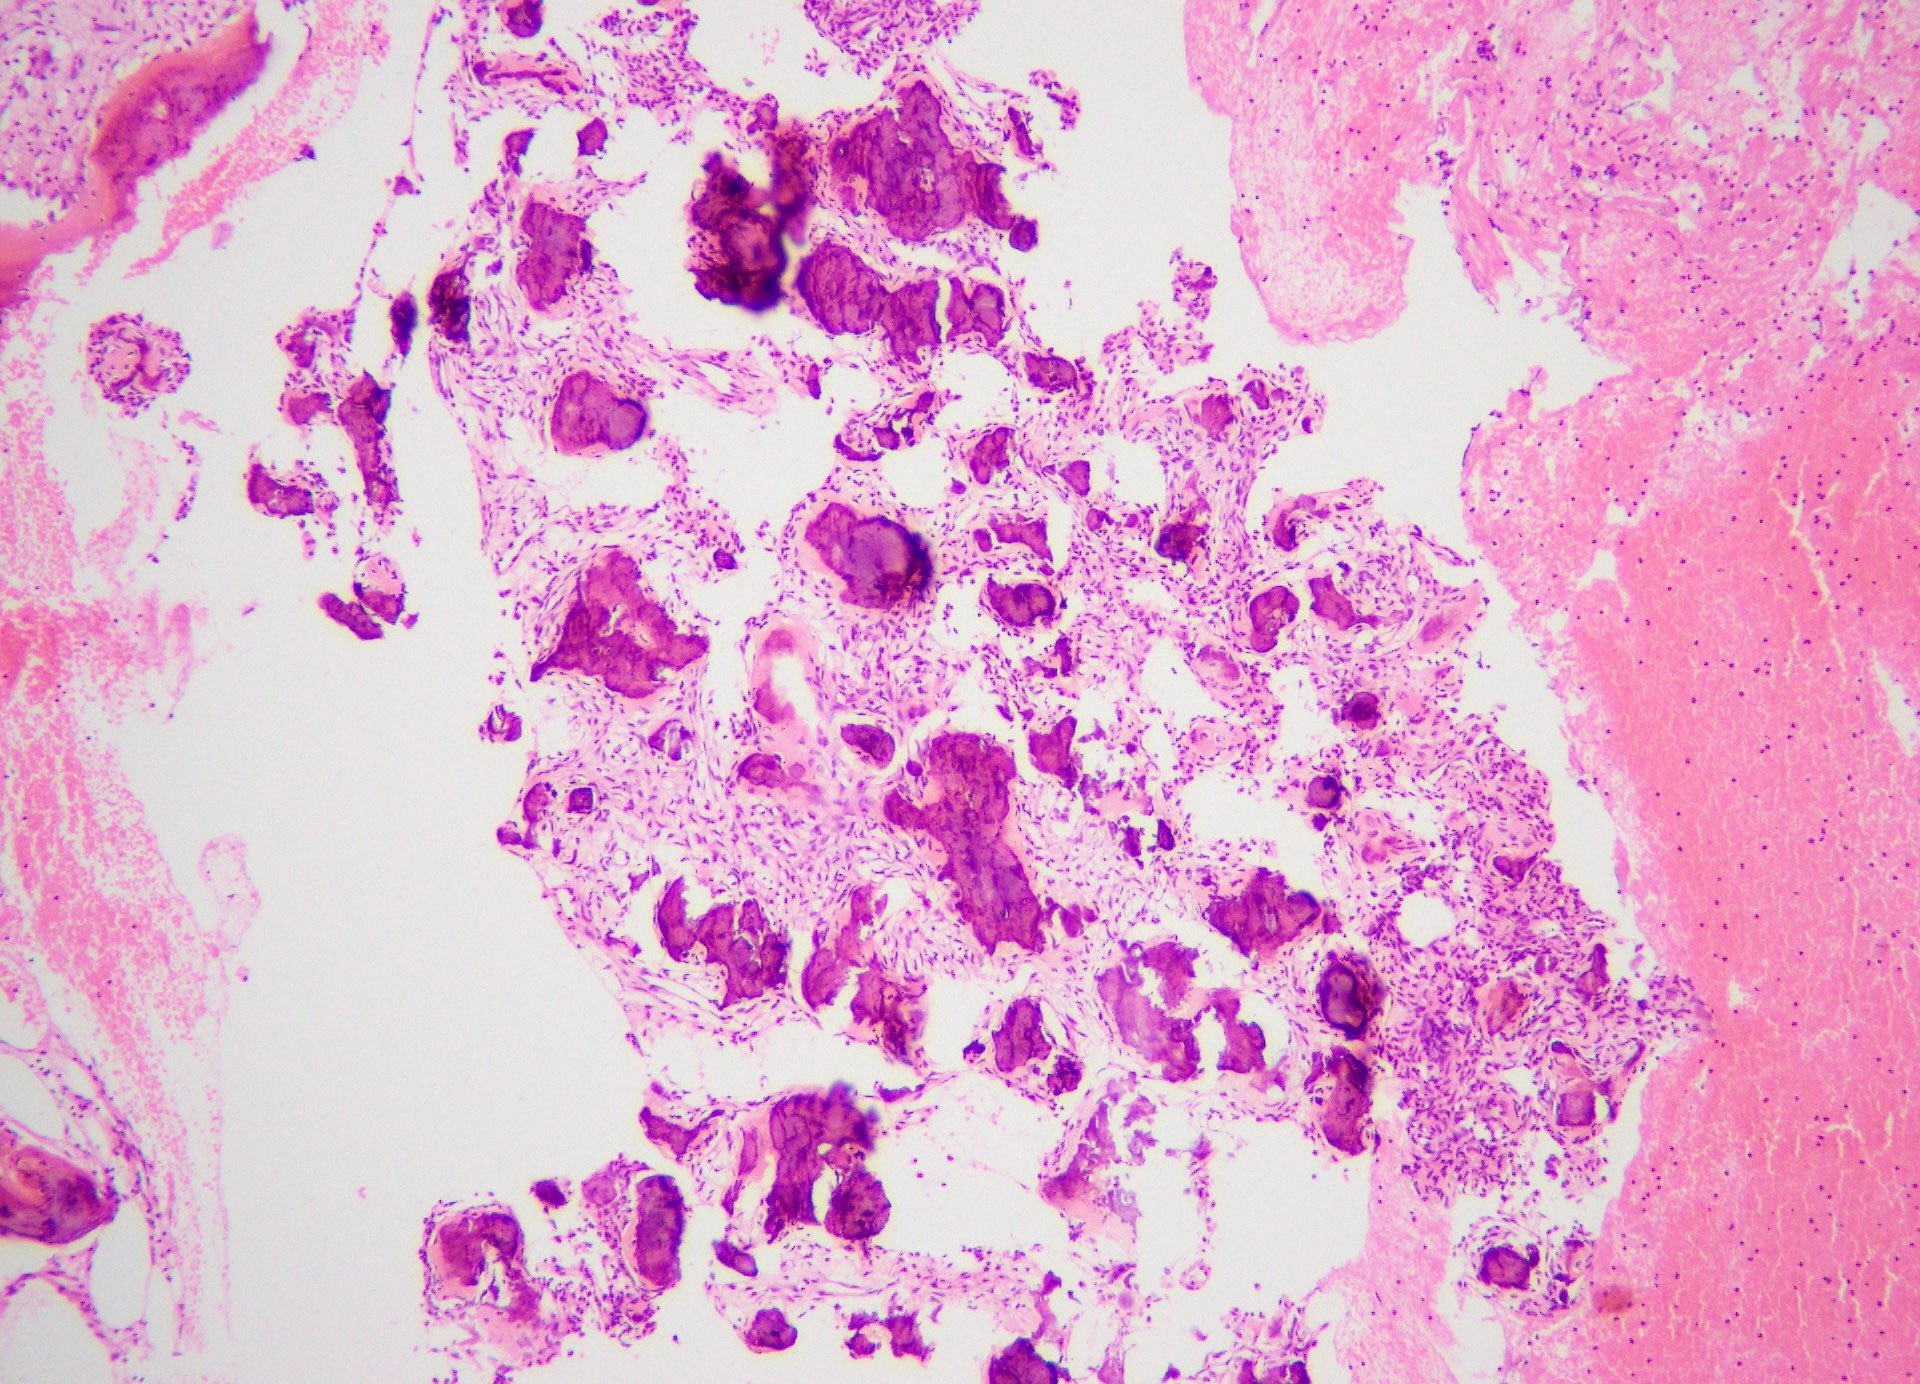

Microscopic (histologic) description

- Well defined lesion; may have thin fibrous capsule

- Well demarcated margin from surrounding normal bone

- Lesion consists of variable proportion of fibrous and mineralized tissue, more heavily mineralized centrally; it shows variation in the amount and type of mineralization, even within a single lesion

- Osteoblastic rimming of bone trabeculae is frequent (J Stomatol Oral Maxillofac Surg 2022;123:364)

- Stroma is fibroblastic with areas of hypercellularity and nuclear hyperchromasia

- No significant atypia and mitoses are infrequent (Head Neck Pathol 2020;14:70)

- Woven to lamellar bone, osteoid and dense acellular or paucicellular basophilic rounded cementum-like calcifications may all be present (Head Neck Pathol 2020;14:70)

- Bony trabeculae may form thick anastomosing strands or fuse into large sheets centrally

- Hemorrhagic cystic degeneration, resembling aneurysmal bone cyst formation, is more often found in juvenile active ossifying fibromas but has been reported in rare COFs (J Stomatol Oral Maxillofac Surg 2022;123:364, Head Neck Pathol 2022;16:248)

- Areas resembling cemento-ossifying fibroma may be seen in psammomatoid and trabecular ossifying fibroma; cemento-ossifying fibroma may contain ossicles like psammomatoid ossifying fibroma

Microscopic (histologic) images

Contributed by Saira Javeed, M.B.B.S., M.Phil., Kelly Magliocca, D.D.S., M.P.H. and Molly Housley Smith, D.M.D.